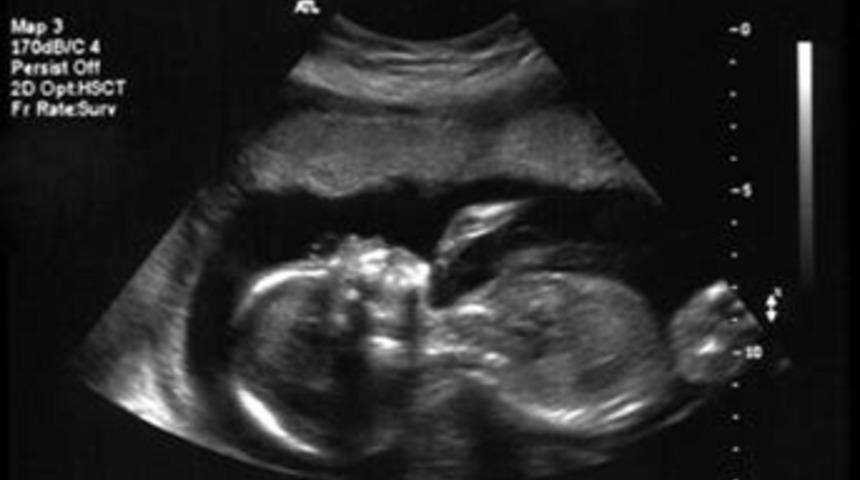

Teknokolik veya teknofobik bir karaktere dönüşmemizi henüz anne karnında maruz kaldığımız hormonlar belirliyor.

Bilimcilere göre teknofobi olarak adlandırılabilecek bu teknoloji kullanma korkusu henüz anne karnındayken şekilleniyor. İngiltere Bath Üniversitesi’nden araştırmacılar, kişinin gelecekte yeni teknolojilere duyacağı ilgi düzeyinin, daha embriyo aşamasındayken maruz kalınan hormonlarca belirlendiğini düşünüyorlar.

Yayınlanan çalışmaya göre doğum öncesi salgılanan testosteron miktarı, beyin gelişimini teknolojiyi kolay veya zor anlayan bir yapıya itecek şekilde etkiliyor. Çalışmanın başındaki Dr Mark Brosnan bu testosteron maruziyetinin doğumdan yıllar sonra dahi etki göstermesinin son derece ilginç olduğuna dikkat çekiyor. Hormonun düşük seviyelerde salgılanmasıyla birlikte kişide, bilgisayar gibi sürekli gelişmekte olan teknolojik cihazları kullanmaya yönelik bir ilgisizlik hatta fobi gelişebiliyor. Üstelik araştırmacılar yaptıkları testlerde, bilgisayar bilimlerinde öğrenim gören öğrencilerin doğum öncesi testosterona maruz kalma düzeylerinin, hipotezi destekler biçimde yüksek olduğunu ortaya çıkarmışlar.